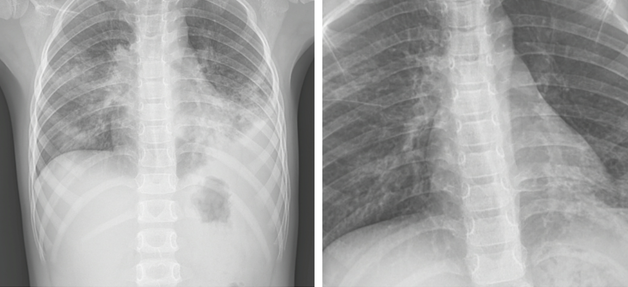

Sau khi khai thác tiền sử và thăm khám lâm sàng, chụp X-quang, các bác sĩ đã chẩn đoán đây là trường hợp viêm phổi thùy/theo dõi tràn dịch màng phổi.

Bệnh nhi được hội chẩn chụp CT scan ngực cho thấy hình ảnh tổn thương đông đặc, kính mờ, nốt mờ ở thùy trên và thùy dưới 2 bên phổi, siêu âm màng phổi có hình ảnh tràn dịch màng phổi trái 13mm.

Phim X-quang tim phổi bệnh nhi trước và sau điều trị. Ảnh: BVCC

Kết quả xét nghiệm Mycoplasma Pneumoniae Real-time PCR dương tính. Sau hơn 1 tuần điều trị, bệnh nhi đã hết sốt, giảm ho, các tổn thương trên phim phổi đã cải thiện.